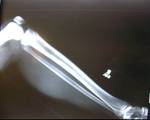

Unilateral tibia lengthening in 16year old girl using ISKD

Immediate Post Op

Lengthening proceeding well

Good regenerate formation with 5cm lengthening